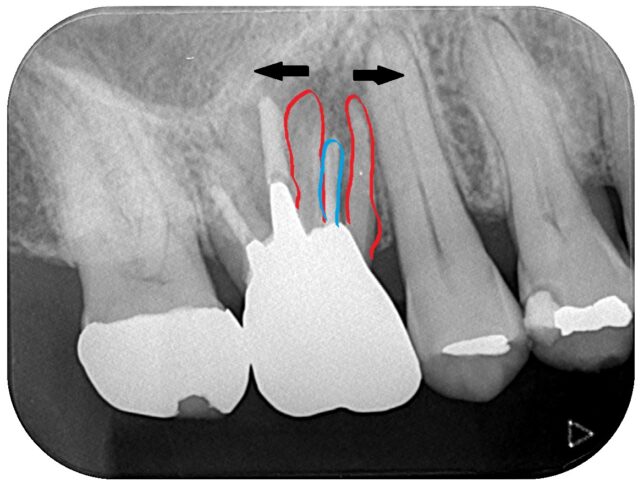

歯根破折といって、歯の根が割れてしまった歯のレントゲン画像です。

解説します。

赤の2本は、元々1本だった根っこが割れて、2つに裂けてしまった状態です。

真ん中の青いのは根管充填剤といって、歯の神経を抜いた管に詰める固形の薬です。

骨折しても、骨はくっついて治りますが、歯の根っこは割れてしまうと、

くっつくことはありません。